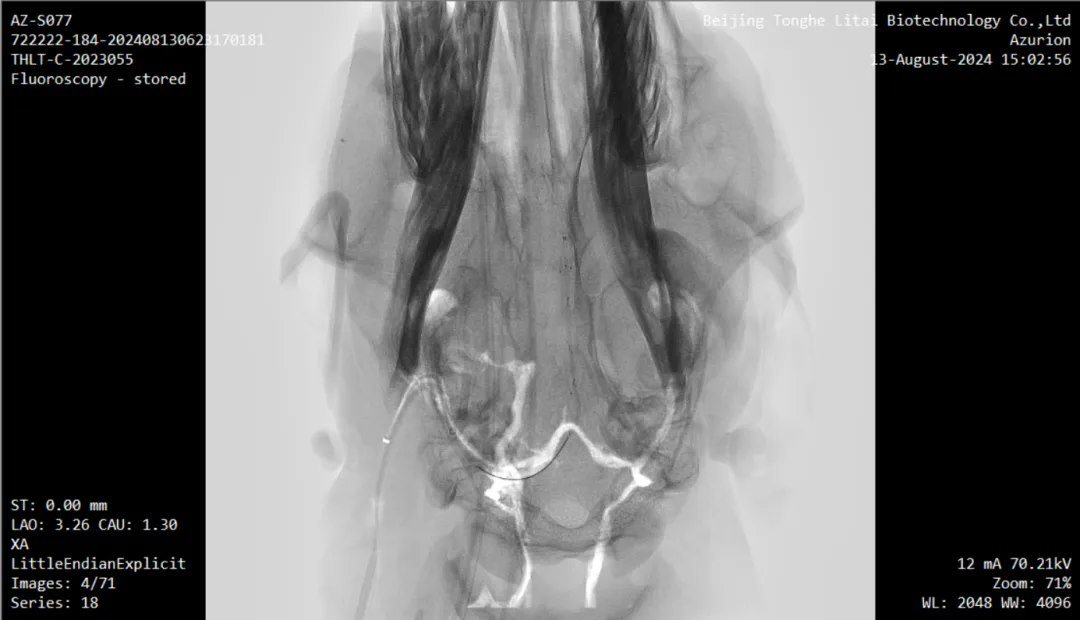

本次试验是在前期两项试验基础上取得的进一步成果。内容包括:将无线传输设备植入实验动物皮下,并将采集到的介入式脑电信号通过无线传输设备传出,实现了稳定、高效的信号传输;以及通过介入手术将先前导入羊颅内血管壁上的介入式脑机接口传感器安全取出,整个过程在 DSA 造影引导下进行,确保了手术过程的安全性。